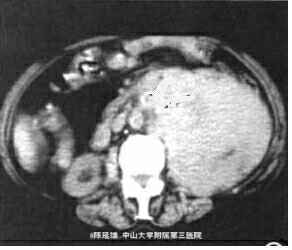

影像学表现:CT平扫,左肾区巨大、不规则形包块,其后内见片状低密度坏死灶,右内近边缘处另见2枚高密度影,肿块最大层面直径约13.2 cm×12.2 cm,周围结构受压移位,部分结构与肿块界限欠清。DSA提示:相当于左肾位置似见左肾动脉、左肾轮廓及其动脉的正常分支,未见明显肿瘤血管,腹主动脉其他部位未见明确动脉分支向“假肾影”供血。DSA诊断肾细胞癌证据小足,遂放弃介入治疗。左肾区肿块穿刺活检病理:小细胞性恶性肿瘤,考虑为恶性淋巴瘤,免疫组织化学染色CD20普遍阳性,支持B细胞淋巴瘤。行标准B细胞淋巴瘤化疗。